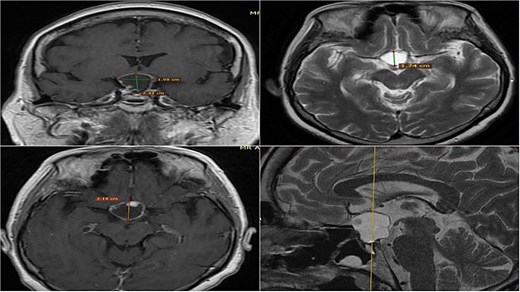

A 71-year-old woman who gradually began with bitemporal hemianopia, progressing to amaurosis of the right eye, adding diabetes insipidus. An MRI study obtained the following images (Fig. 1). 3D reconstruction was performed by manual segmentation to obtain the anatomy of the tumor and its vascular relationships. For this segmentation, it was necessary to splice T2, T1, Contrast, and 3D TOF sequences (Fig. 2). The importance of the reconstruction lies in being able to adequately observe most of the cerebral blood circle and its relationships with the tumor. At the time of carrying out the transnasal resection surgery and keeping in mind the proximity of the anterior communicating artery with the dorso-ventral region of the tumor, the capsule was resected with excessive caution to avoid generating excessive traction and thus avoiding injuries—important vascular (Fig. 3).

3D reconstruction through manual planimetric segmentation of the tumor and its vascular relationships. White arrow, left internal carotid artery. Yellow arrow, anterior cerebral artery segment A2. Red arrow, anterior communicating artery.

Surgical images. White arrow, anterior communicating artery. Yellow arrow, tumor capsule.